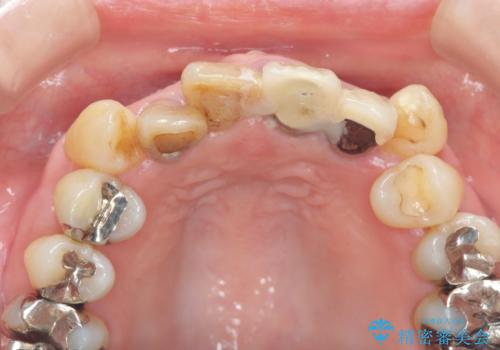

- 前歯のぐらつき、見た目の改善を希望され来院されました。

ぐらつきのある歯は、破折が認められ、その他前歯も不十分な根管治療や不適合なクラウン、レジン修復により審美障害が起きています。

問題を一つづつ丁寧に解決し、前歯の審美性の改善を計画します。